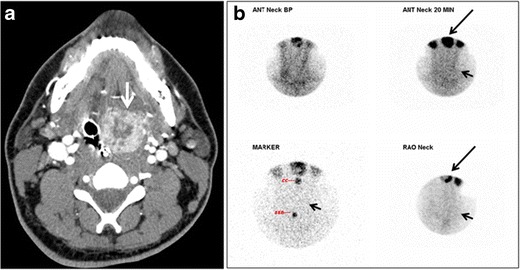

I-131 radioactive uptake studies are useful to further characterize nodules.

Increased uptake (hot nodule) is seen in Graves’ disease or nodular goiter.

Decreased uptake (cold nodule) is seen in adenoma and carcinoma and they often warrant biopsy.

Biopsy is performed by fine needle aspiration (FNA).